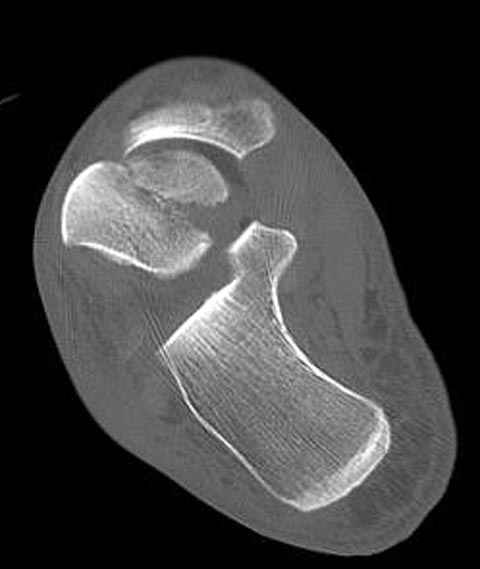

Вдогонку по поводу перелома таранной кости, больная 81, не страдает диабетом, перелом закрытый, в первый же день поступления ограничились временным наружным фиксатором (как на снимке).

За пару недель насчитал 5 больных с переломом таранной кости, из них двое с двусторонним повреждением.

Из-за отека на стопе тактика лечения у всех была

одинаковая: временная наружная фиксация до спадения отека, при изолированных переломах они выписывались домой и через дней 7 госпитализировались на оперативное лечение.

Примеры на снимке...